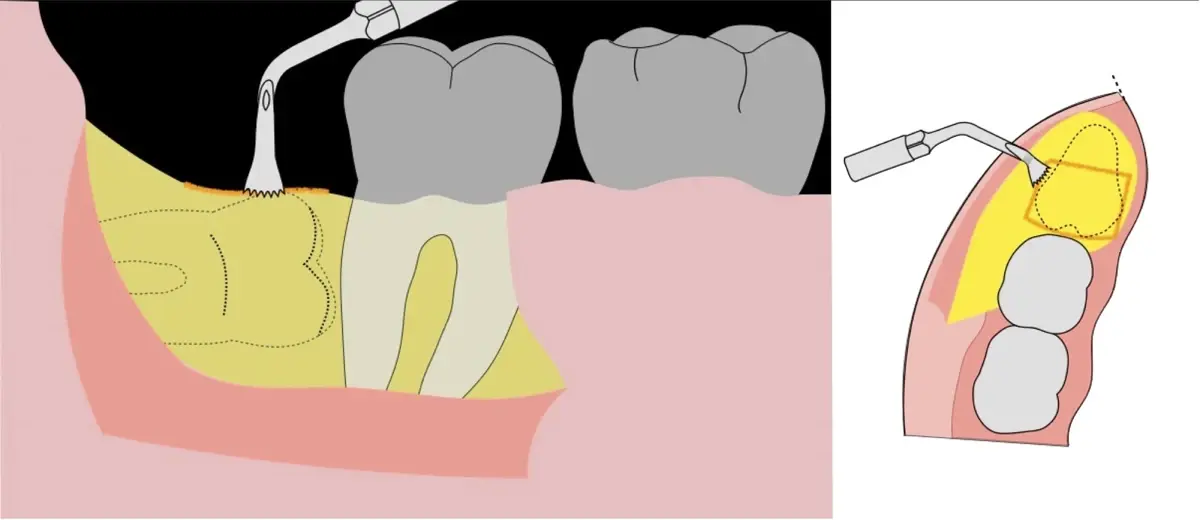

Figura 8. Odontosección mediante fresa de alta rotación y/o inserto de corte de piezoeléctrico. Posteriormente se procede al ensanchamiento del espacio pericoronario con el periótomo de piezoeléctrico para facilitar la avulsión de la pieza dentaria.

Figura 9. Avulsión de la parte coronaria de la tercera molar.

Figura 10. Tracción mesial del remanente dentario utilizando botadores en bandera.